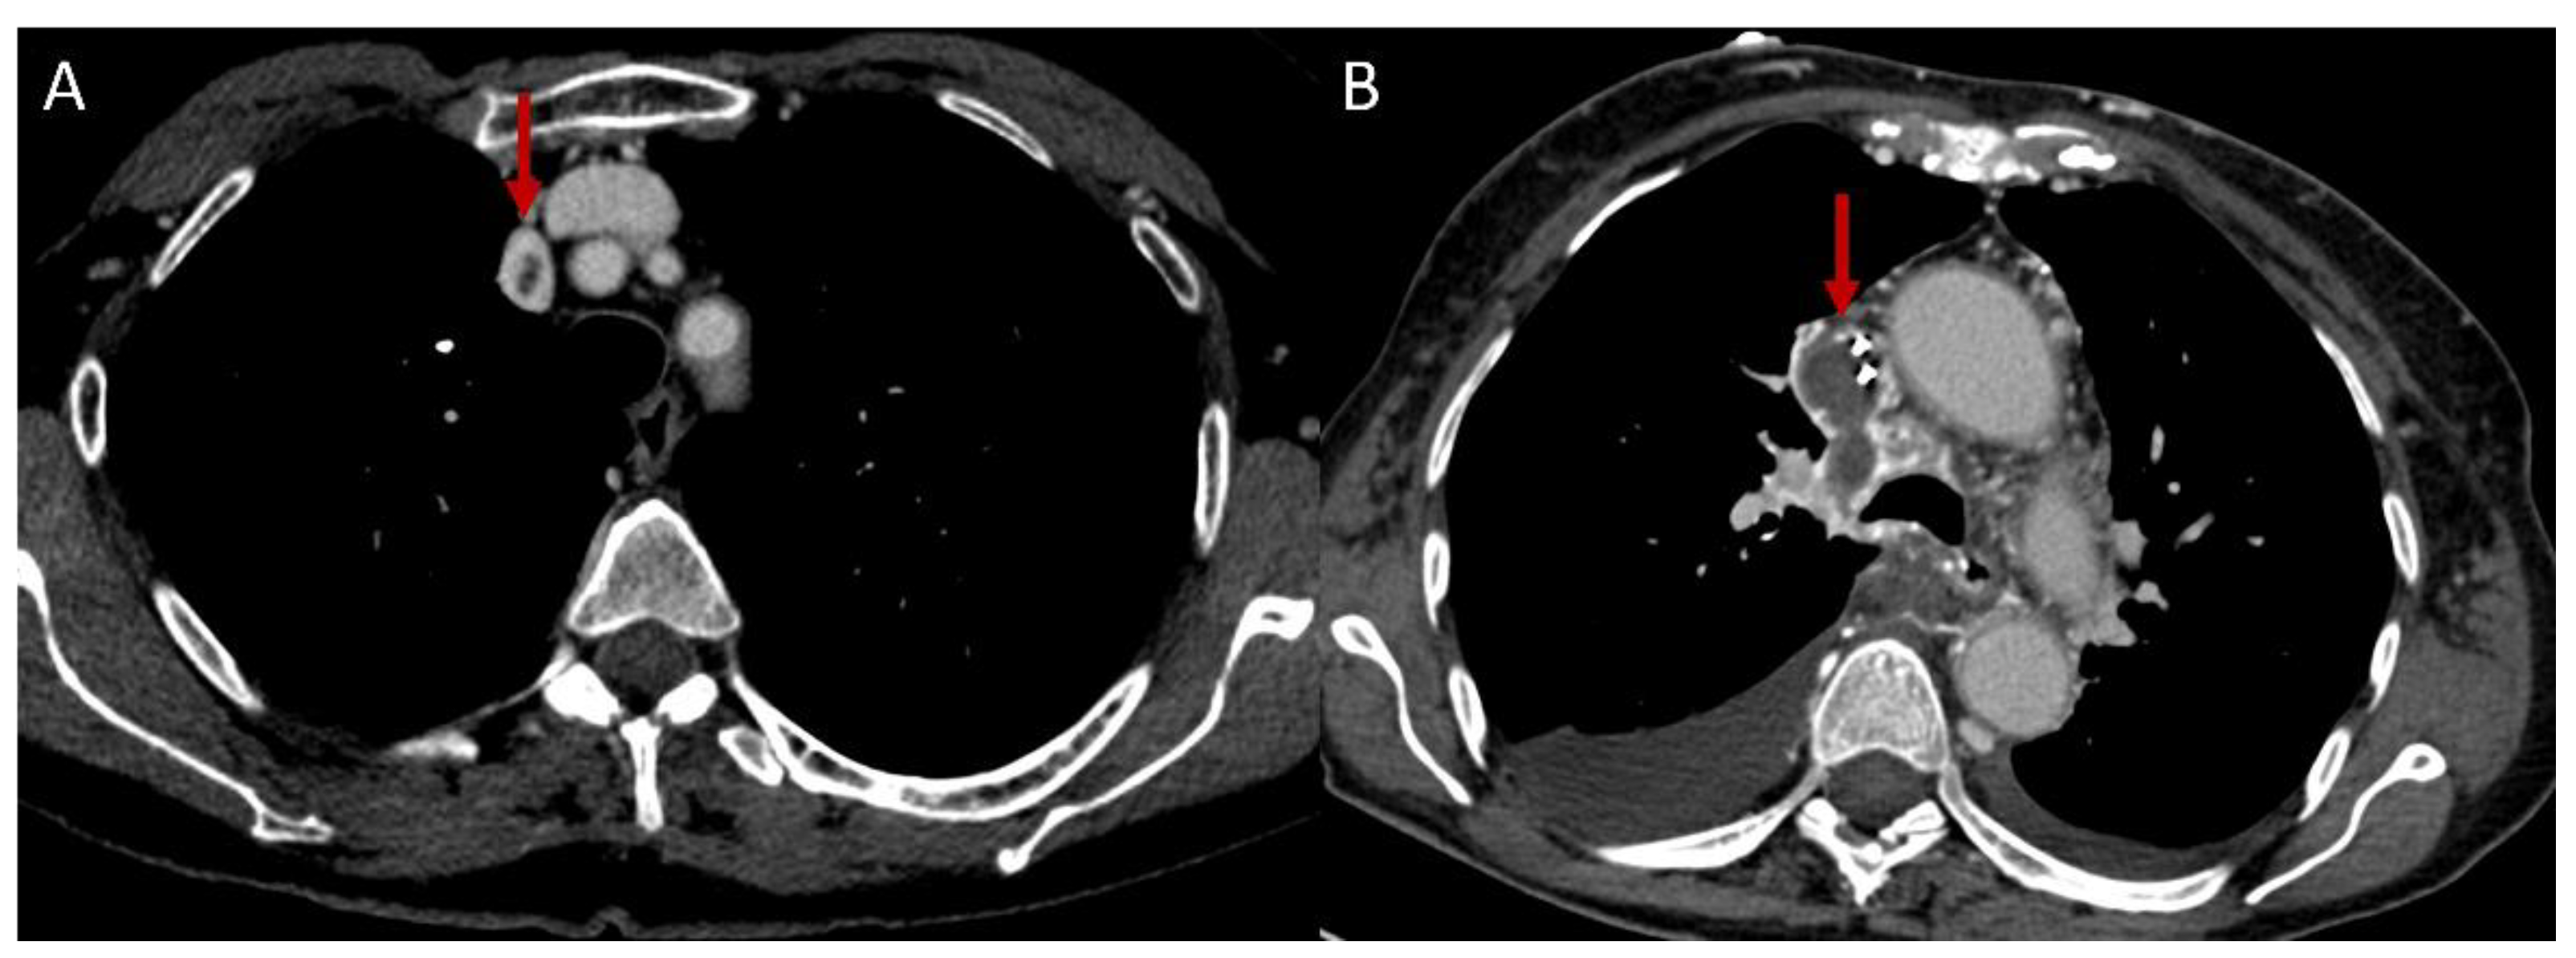

2.1.3. Systemic Veins

- Sheth, S.; Ebert, M.D.; Fishman, E.K. Superior Vena Cava Obstruction Evaluation with MDCT. AJR Am. J. Roentgenol. 2010, 194, W336–W346. [Google Scholar] [CrossRef]

- Qanadli, S.D.; el Hajjam, M.; Bruckert, F.; Judet, O.; Barré, O.; Chagnon, S.; Lacombe, P. Helical CT Phlebography of the Superior Vena Cava: Diagnosis and Evaluation of Venous Obstruction. AJR Am. J. Roentgenol. 1999, 172, 1327–1333. [Google Scholar] [CrossRef]

- Zhou, J.; Zhang, D.; Wang, Z.; Hou, Y.; Liu, J.; Zeng, X.; Wang, Y.; Zheng, W.; Zhou, J.; Zhang, D.; et al. The Clinical Features, Image Findings and Risk Factors of Vena Cava Syndrome in Behçet’s Syndrome Behçet’s Syndrome with Vena Cava Syndrome. Clin. Exp. Rheumatol. 2022, 40, 1526–1534. [Google Scholar]

- Temizöz, O.; Genchellac, H.; Yekeler, E.; Demir, M.K.; Ünlü, E.; Özdemir, H. CT-Angiographic Demonstration of Hepatic Collateral Pathways Due to Superior Vena Cava Obstruction in Behçet Disease. Diagn. Interv. Radiol. 2010, 16, 302–305. [Google Scholar] [CrossRef]